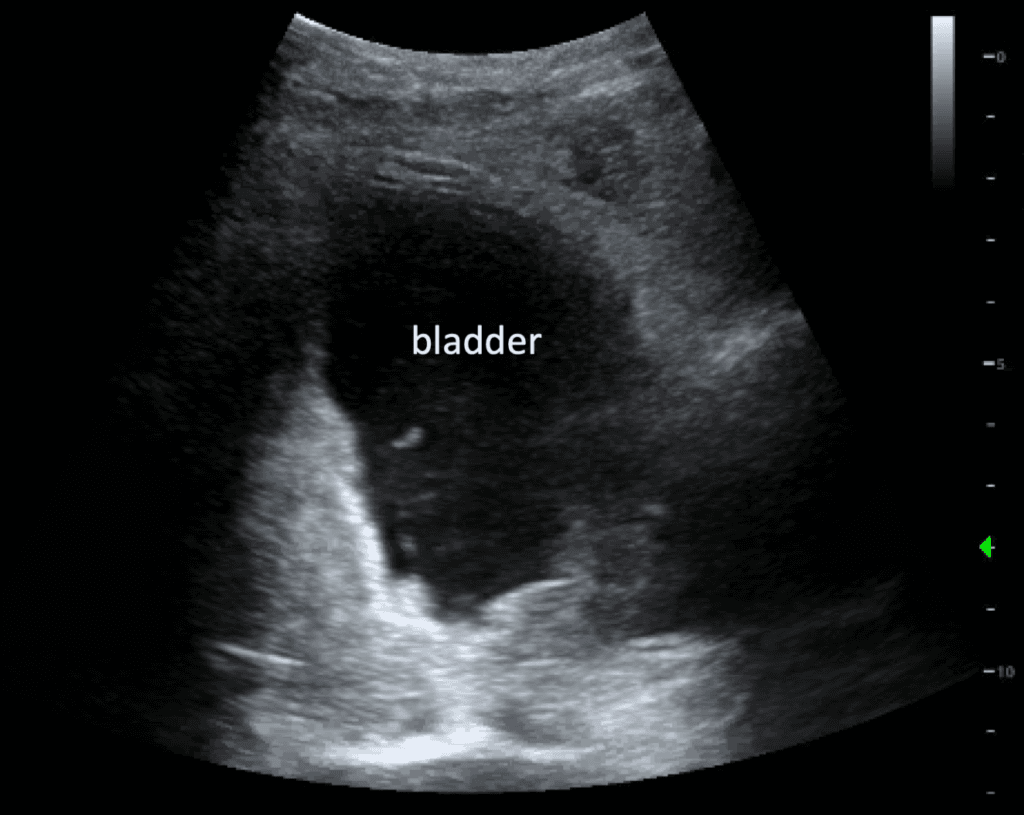

from pocusjournal.com

Delayed Iatrogenic Bladder Rupture Diagnosed by POCUS in the Emergency